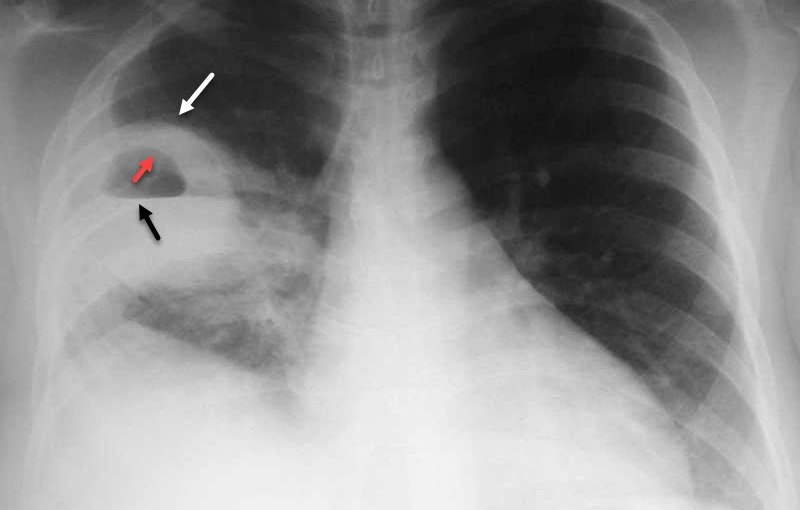

Trẻ nhiễm virus hợp bào hô hấp đang gia tăng2Bệnh viêm phổi do virus RSV được nhìn thấy trên phim chụp X-quang